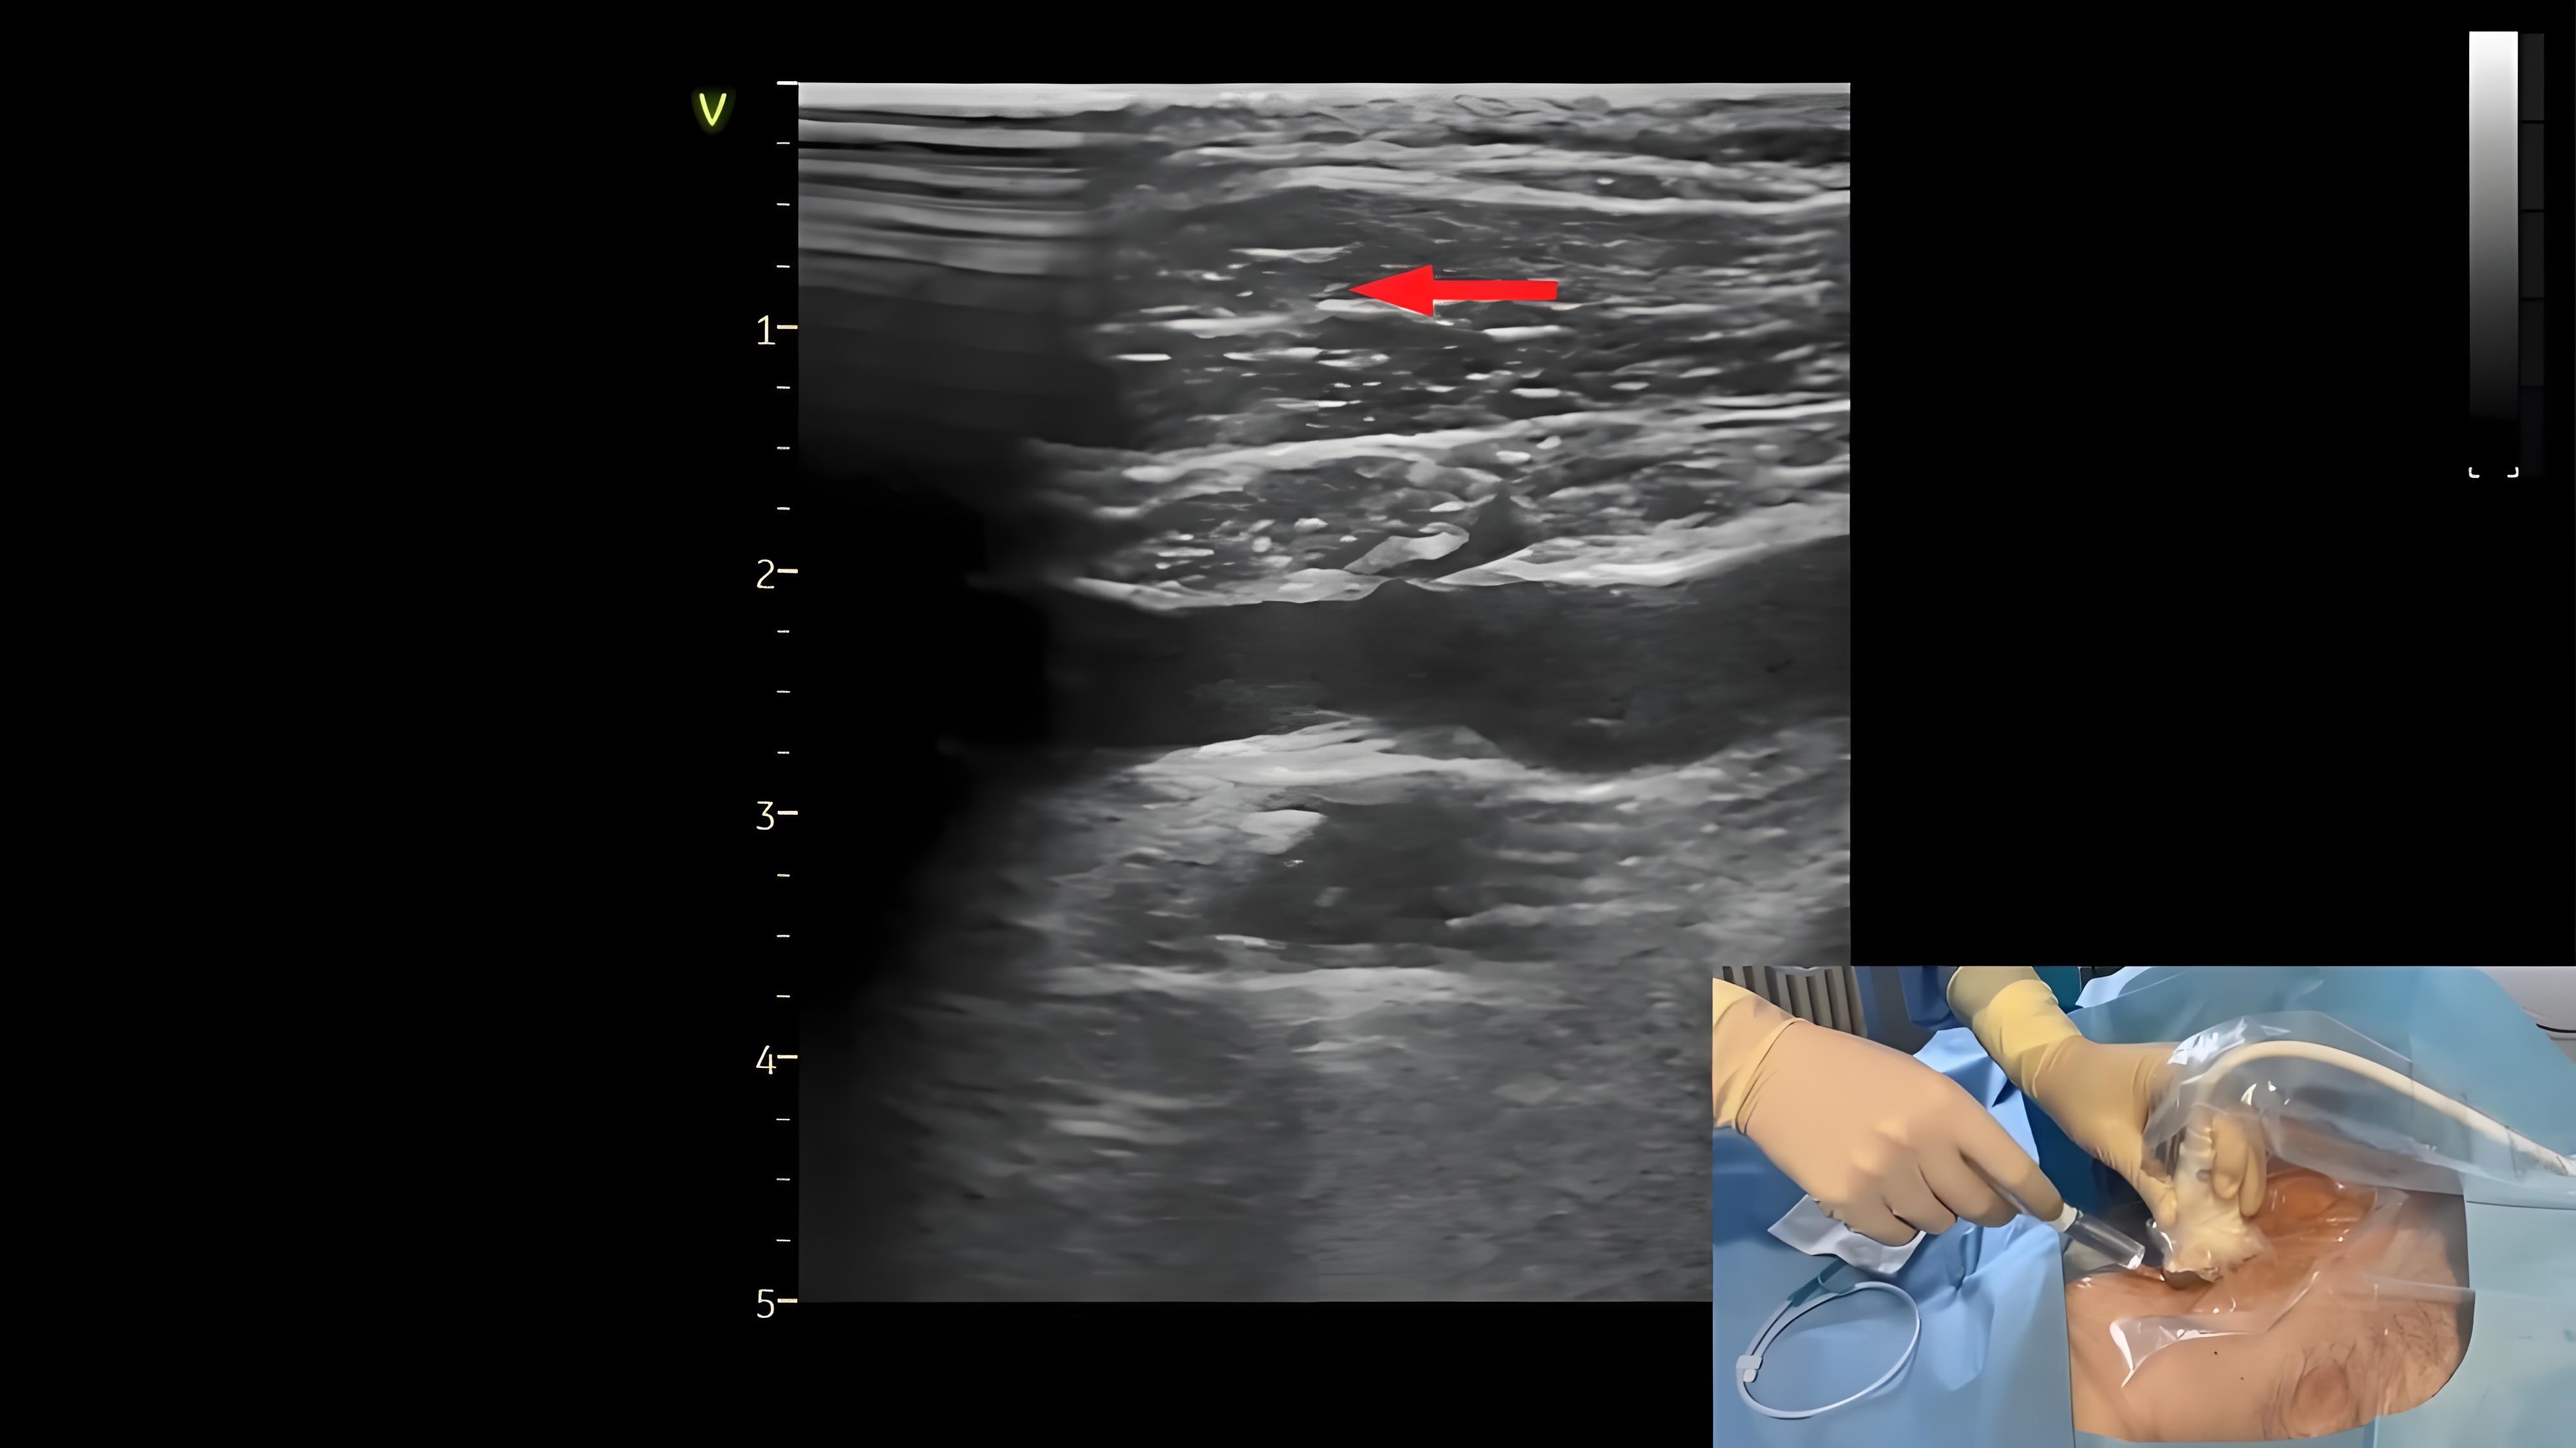

超声引导平面内锁骨下静脉穿刺置管

121 #锁骨下静脉穿刺